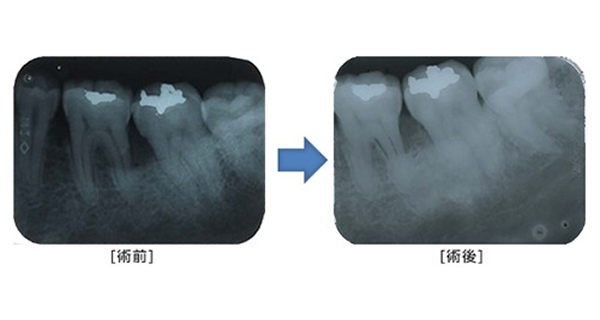

歯周外科